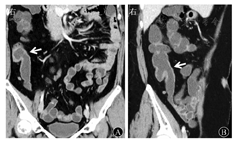

回盲瓣挛缩变形表现为回盲瓣位置抬高上提,这与病变修复过程中的纤维组织增生和瘢痕收缩有关。回盲瓣固定开口表现为受累回盲瓣呈"鱼嘴样"张开,并持续开放,形态固定不动(图1)。刘小伟等[6]对122例肠结核患者内镜下表现进行研究,结果发现50.8%的患者表现为受累回盲瓣固定开口。Zhao等[5]对141例CD患者和47例肠结核患者的CTE表现进行了鉴别诊断,并对有意义的单变量指标进行了Logistic回归分析,建立了数学回归方程,发现回盲瓣挛缩变形和固定开口这2个征象的特异度较高,分别为94.3%和97.9%。